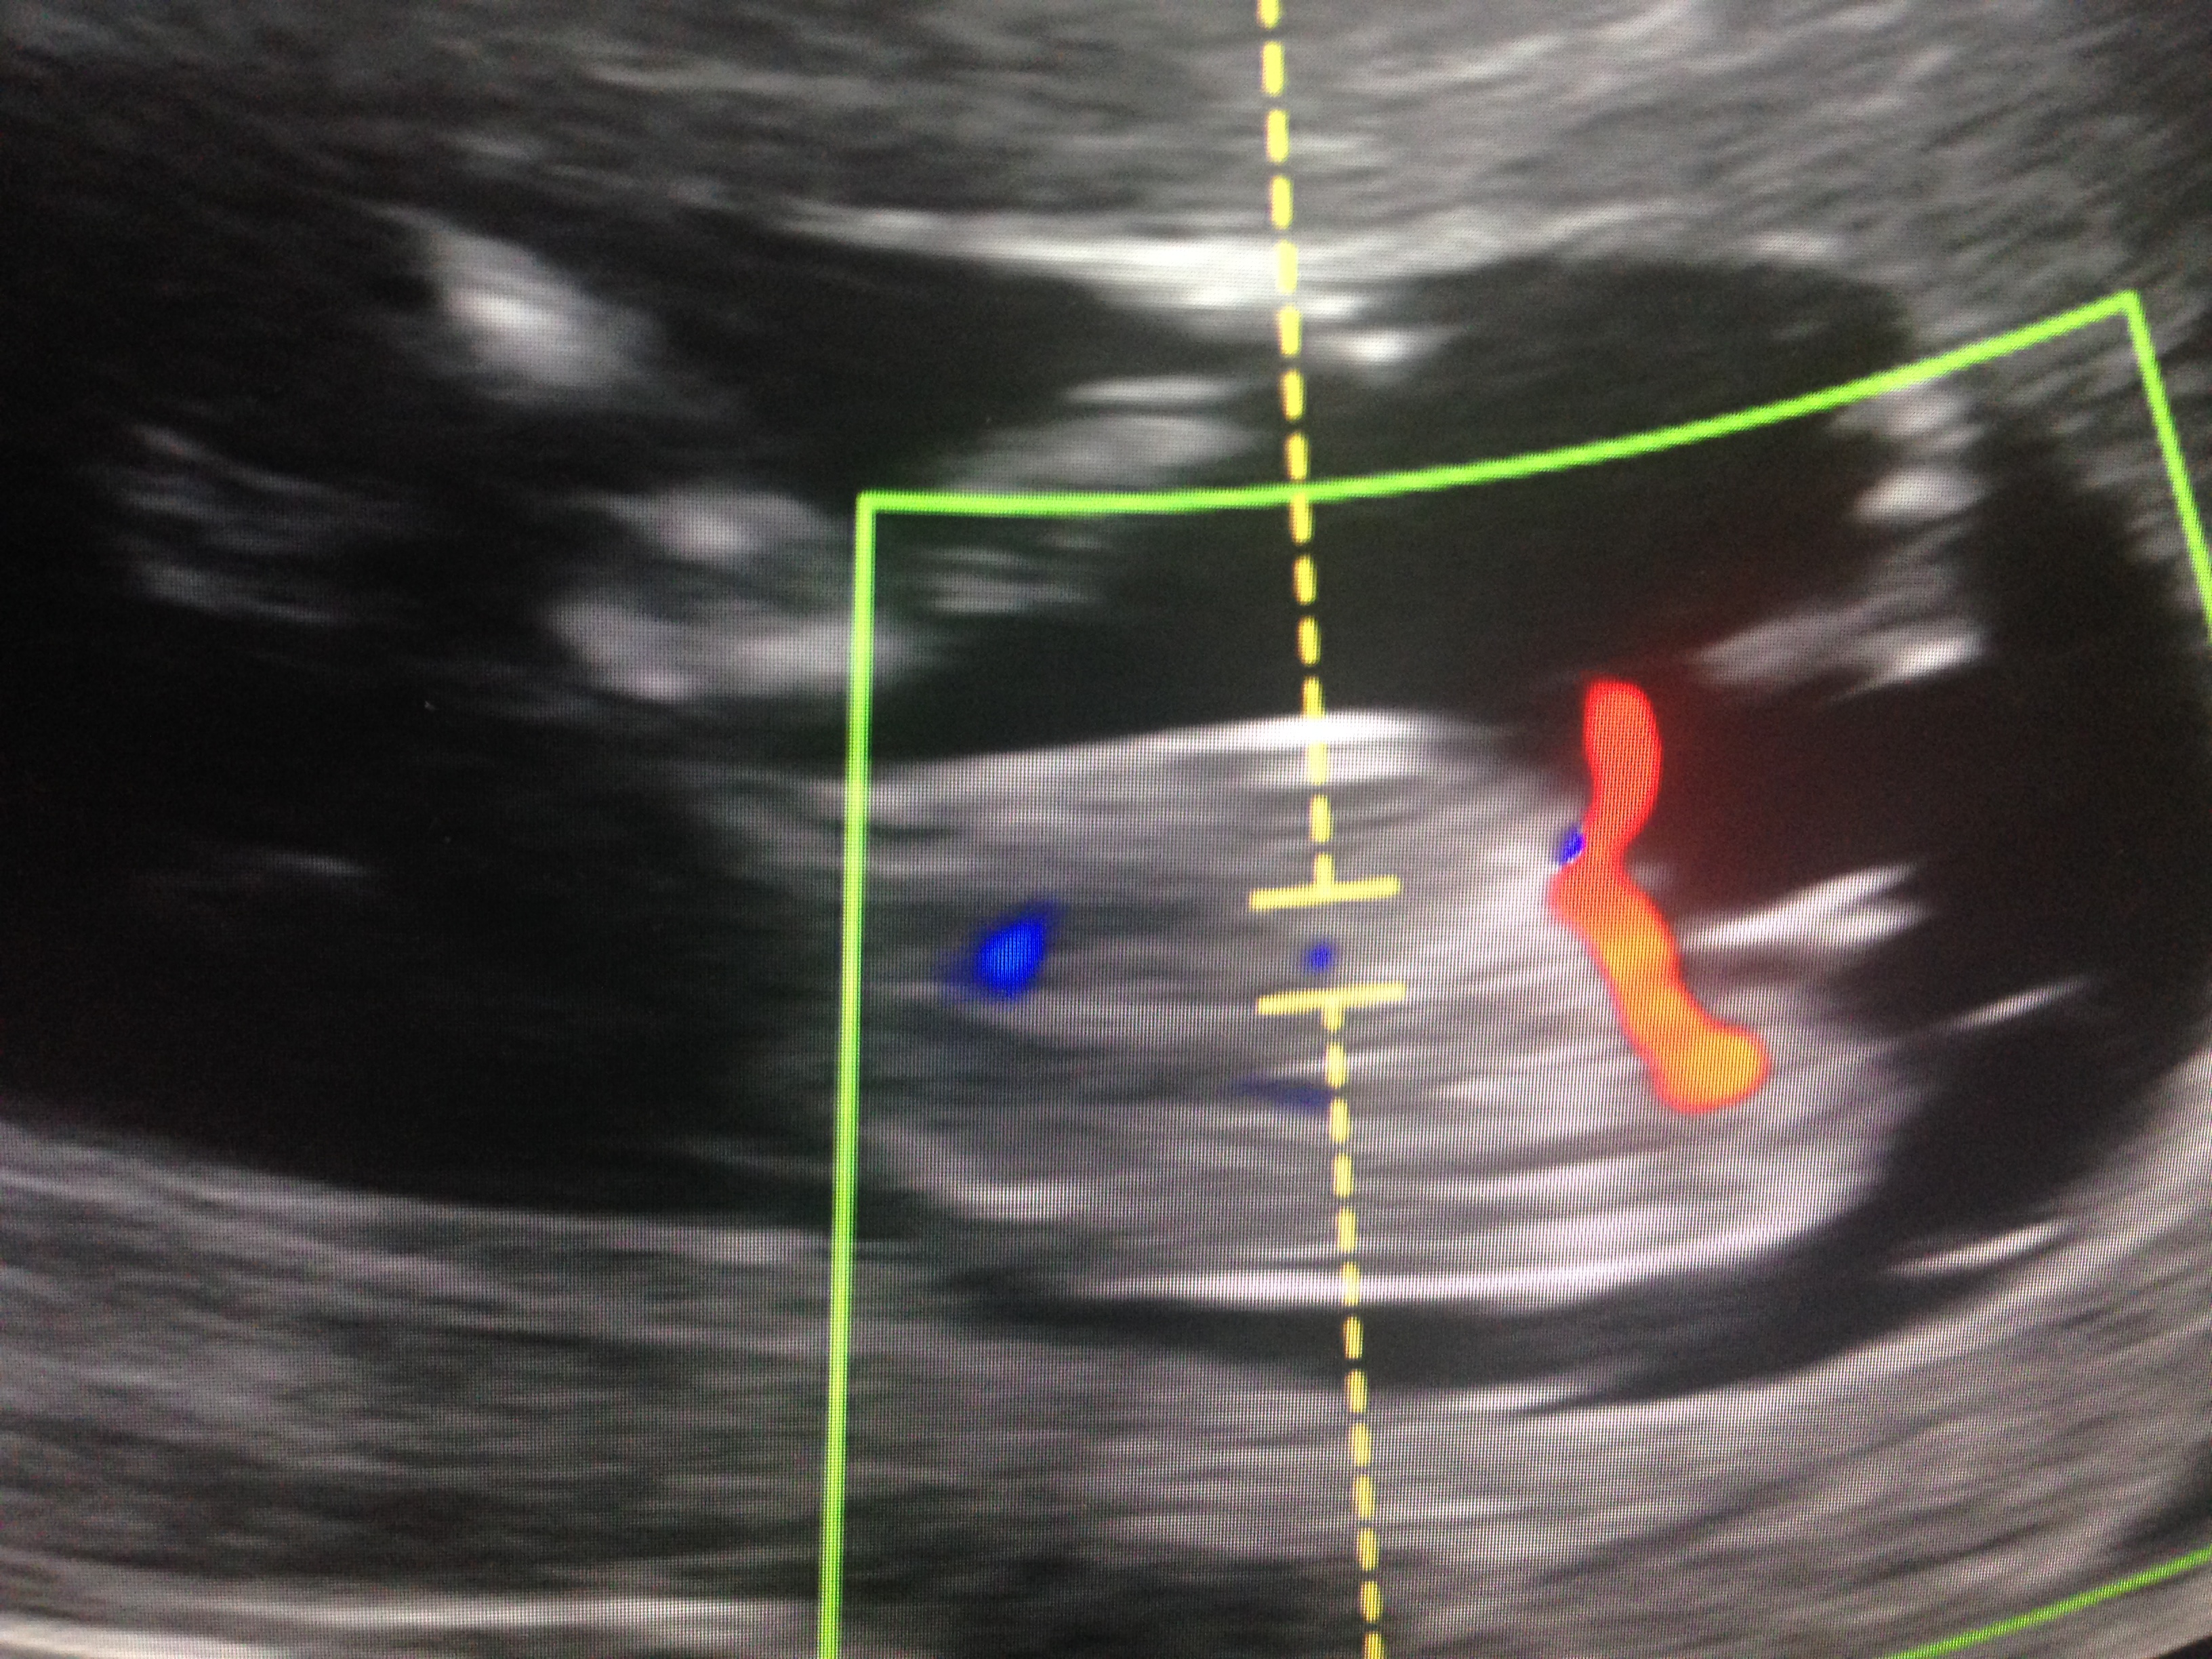

I would say boy, but since baby is not lying flat , I can't work out the angle accurately.

Any opinions would be appreciated!

Is it exactly 12 weeks or 12 weeks and a few days? It looks girly so far at least, but if it were 12+0 or 12+1 it could still be a but too early to tell.

it's 12weeks 0days so i guess it could still be on the upward rise.

Looks a bit angled for 12 weeks but shape looks girly. Tentative boy lean but could be baby's positioning throwing off angles. I don't think nubs can go down.